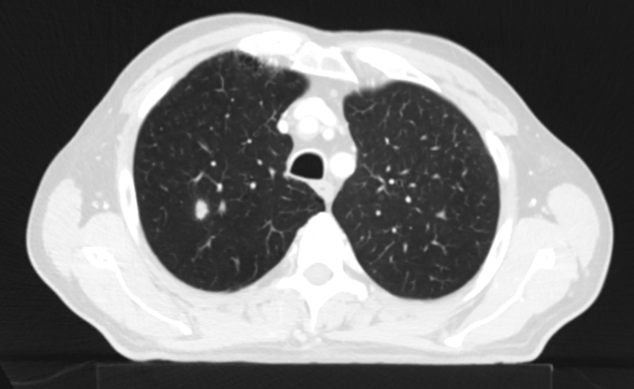

Řez plicemi z CT screeningu: Kontrolní  CT plic před zahájením léčby pembrolizumabem v 10/2021

Obr 2. – Kontrolní  CT plic před zahájením léčby pembrolizumabem v 10/2021.